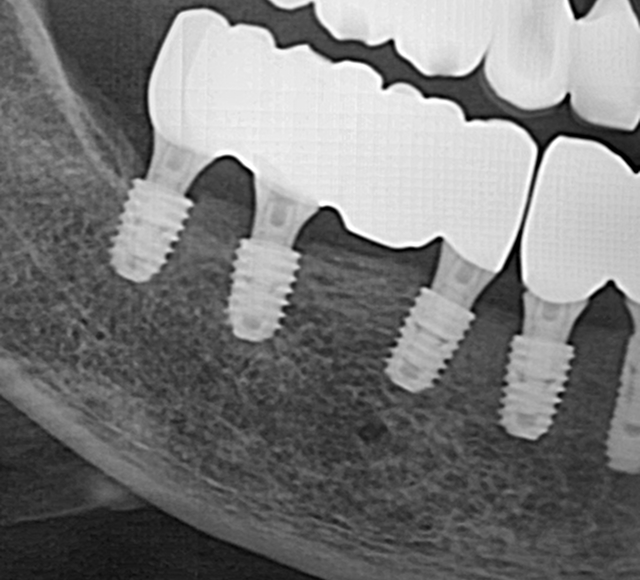

고난도 뼈이식 케이스

- 정밀 영상 진단으로 결손 부위를 파악하여 안전하게 골이식

- 미세 수술 장비를 활용해 식립 안정성 및 성공률 향상